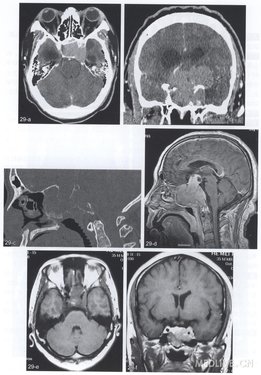

【简要病史】3个病例。例1(图29a,b),男,35岁。左眼失明、右眼视物模糊半年,伴头痛,加重6天。例2(图29c,d),男,57岁。视力下降3个月,体检可见鼻后孑L肿物。例3(图29e,f),女,36岁。头痛6个月,伴左侧面部麻木。

【CT与MRI所见】例1,增强CT(图29a,b)示蝶鞍增大,鞍上池消失,鞍区巨大分叶状明显强化肿物,最大径5.9cm,左侧颈内动脉海绵窦段及以上、左侧大脑中动脉被包绕。例2,矢状位CT重组(图29c)示蝶骨体及斜坡弥漫性破坏。T1WI增强(图29d)鞍底为中心巨大强化性肿物,向后累及斜坡,下方到达鼻咽顶部。例3,轴位T1WI平扫及冠状位增强T1WI(图29e,f)显示鞍内偏左侧等信号及明显强化的肿块,左侧颈内动脉包绕及狭窄。

【手术后病理诊断】侵袭性垂体瘤。

【影像学特点】鞍区分叶状巨大肿块,以蝶鞍或鞍底为中心,可蔓延至蝶窦一鼻咽顶部、斜坡、单侧或双侧海绵窦、眶尖,向上压迫视交叉、第三脑室、下丘脑,向后上填塞脚间池及桥前池,甚至可压迫大脑脚及脑桥,海绵窦为肿块占据,颈内动脉被包绕。CT多方位重组图像对骨质改变显示较好,增强扫描及CTA能显示肿块与颈内动脉及海绵窦的关系,MRI对IPA侵犯范围显示更佳,并能清楚分辨正常海绵窦强化与肿瘤侵犯,后者强化程度低于正常海绵窦,但必须仔细调节窗值观察,窄窗宽及低窗位可造成漏诊。CT与MRI-般采用Knosp法分级:1级,肿瘤到达颈内动脉内侧壁连线;2级,肿瘤到达颈内动脉中心连线;3级,肿瘤到达颈内动脉外侧壁连线;4级,肿瘤超过颈内动脉外侧壁连线;5级,肿瘤包绕颈内动脉。但该方法未考虑到肿瘤对蝶窦、眶尖、斜坡及脑组织侵犯。